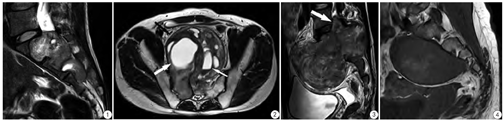

(1)瘤体呈膨胀性生长、包膜完整的软组织结节,大小不一。7例见哑铃状改变,其中2型2例、3型5例。包膜于T1WI、T2WI上均为低信号(图2)。(2)瘤体边缘光整的6例;分叶状的20例,其中12例可见足状突起,表现为分叶状边缘之外单个或数个齿轮状隆起嵌入邻近组织内,宽3~10 mm、长7~15 mm不等(图6,图7)。笔者称之为"足突边缘"征。(3)椎管外骨质改变:1例瘤体跨骶髂关节破坏一侧髂骨(图7) ;4型的2例分别见S1、S2椎前局灶性骨质压迫吸收。

(1)以臀肌为参照,瘤体实质T1WI上呈等信号、稍低信号。T2WI上信号不均,呈2区基本信号改变:Ⅰ区,以稍高信号为主,间有部分等信号;Ⅱ区,以高信号为主,间有部分稍高信号与极高信号。Ⅰ区、Ⅱ区间隔排列,排列形式具多样性。两区大小范围,在同一瘤体不同部位及不同病例间变化不一。增强后不均匀强化,Ⅰ区明显强化。Ⅱ区表现出明显差异性强化,自无强化至轻微强化不等,呈T2WI信号越高强化越弱趋势(图8)。(2)瘤内囊变多见,常同时合并出血。囊变灶呈圆形、卵圆形或不规则形液性信号,T1WI呈稍低、等或稍高信号,T2WI上以高信号为主,可单个、多个或累及大部分瘤体,多见低信号囊壁。出血灶呈特征性表现,可见黑白液平征,液平上多呈T1WI稍高、T2WI高信号改变,液平下呈T1WI、T2WI极低信号,壁呈T2WI低或极低信号环(图2)。

已报道的神经鞘瘤MRI-病理对照研究显示,Atoni A区和Atoni B区分别对应T2WI上的稍高信号和高信号[15]。本研究也支持这一结果。本研究显示,瘤体内Ⅰ区、Ⅱ区的T2WI信号表现与其强化效应存在关联。MVD低的Ⅰ区较MVD高的Ⅱ区强化显著,有悖于强化效应随MVD增高而增强的一般规律,其原因在于强化效应取决于诸多因素的作用,除微血管数量外,微血管壁基膜的通透性、组织的渗透压及增强扫描的时机等,均是影响强化效果的重要环节。推测造成这种强化差异的机理在于:(1)组织结构不同,即Ⅰ区、Ⅱ区内瘤细胞与黏液含量比列的差异;(2)微血管壁通透功能不同。Ⅰ区瘤细胞密集、黏液少,产生T2WI稍高信号,但低MVD的管壁通透性高,常规增强扫描时较多对比剂经血管进入瘤细胞区,导致强化效果显著。而Ⅱ区黏液含量高、瘤细胞稀少,产生T2WI强信号,同时高MVD的管壁通透性低,常规增强扫描时较少对比剂经血管进入组织,导致强化效果弱。从组织病理学基础出发,Ⅰ区、Ⅱ区的T2WI信号表现反映了二者瘤细胞与黏液成分构成比例差异的性质,且与差异性的强化效应相对应,因此,这种T2WI双重信号与差异性强化是神经鞘瘤的特征性MRI表现。基于2区比例变化不一,因此在Ⅰ区占主导成分情况下,多层面观察以发现Ⅱ区结构,将有助于确立神经鞘瘤的诊断。

根据骶椎神经鞘瘤在骶椎的三维侵犯特点,结合T2WI上特征性的双重信号及相应的差异性强化,基本可以做出诊断。辨识T2WI双重信号区是诊断的关键,尤其是广泛囊变、出血情形下辨识相当困难,需多层面、多方位观察。与神经纤维瘤的区别是,后者是丛状生长肿瘤,多呈弥漫性分布,无包膜[6]。鉴于MRI上神经鞘瘤的良恶性很难区分[16]。其鉴别常需借助免疫组化分析[16],骶椎神经鞘瘤主要需与脊索瘤、骨巨细胞瘤鉴别。脊索瘤多位于骶椎中线区,T2WI以高信号为主,缺乏神经鞘瘤的T2WI双重信号特点,常规增强扫描上瘤体强化较弱,有别于神经鞘瘤内局部明显强化[3]。骨巨细胞瘤与神经鞘瘤相似,多偏侧生长,但前者倾向于椎后侵犯,肿瘤轮廓欠光整,T2WI多呈低信号。另一需要鉴别的少见肿瘤,是发生于骶椎的巨大破坏性粘液乳头状室管膜瘤,瘤体占据骶椎中线区,溶骨性破坏显著,且T2WI呈高低混杂信号、明显强化,但椎后侵犯相对多见[17]。发生广泛囊变、出血时,需与动脉瘤样骨囊肿鉴别[18]。第4型因其邻近盆腔器官,需注意排除浆膜下型子宫肌瘤[19]。